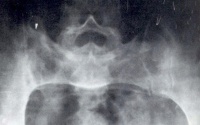

以骶髂关节炎最为突出。骶髂关节出现x线征象时往往已较迟,几乎完全是双侧性。最初出现的是关节附近

退变性骶髂关节炎

有斑片状骨质疏松区,特别是骶髂关节的中下段最为明显。接着便出现了骨腐蚀与软骨下骨皮质硬化。在骶髂关节的中下段,髂骨面覆盖着薄层软骨,因此该处首先出现骨骼变化,且比较明显。在骶髂关节的上1/3处,有坚强的韧带连接着骨面,也可以有类似的X线征象。

软骨下骨侵蚀的X线表现为关节间隙的假性增宽。接下去便是纤维化、钙化、骨桥形成与骨化。一般说来,软骨下骨皮质硬化比骨腐蚀明显些,最终骶髂关节完全强直,通常需数年之久。